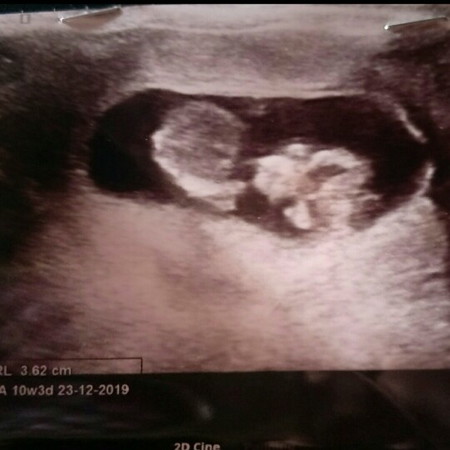

ดุไม่ออกเลยค่ะว่าญรึช

แม่คนใหนดุออกค่ะช่วยดุหน่อยค่ะ

16wถึงจะรู้แน่ชัดนะคะ ตอนนี้แค่10w ปุ่มเพศน้องยังไม่เจริญเต็มที่จ้า แต่ถ้าอยากชัวร์ก็ตรวจเลือดจ้า

ยังเล็กไปค่ะแม่ดูไม่ออกหรอกค่ะ